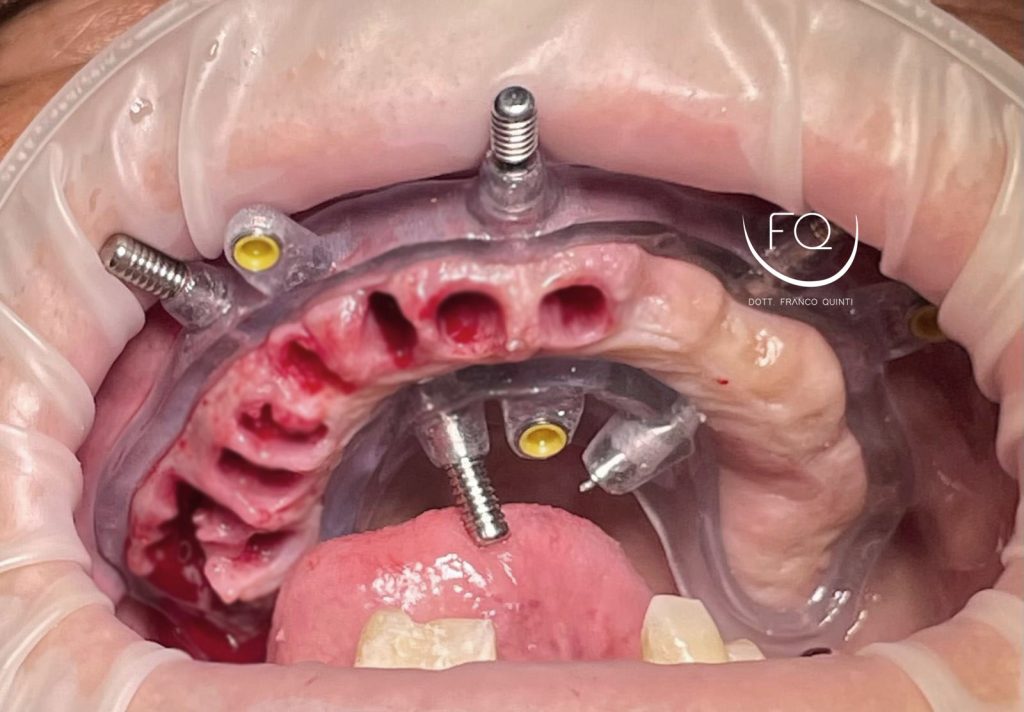

Questa settimana vi presento un caso di chirurgia computer guidata dell’arcata superiore realizzato con dime scomponibili con esecuzione contestuale di un carico immediato.

Nelle prossime settimane vi mostrerò dei brevi video di questo caso relativi alla scomposizione e alla progettazione delle dime chirurgiche.